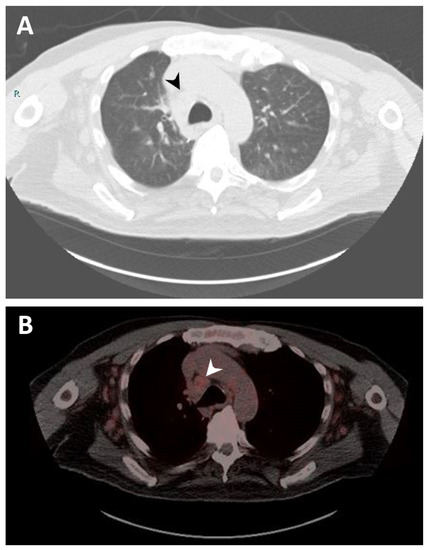

In 2020, the patient was admitted to the hospital due to progressive shortness of breath. Imaging reported increased LUL mass size to 5.9 cm encasing the bronchovascular bundle of the lingula. A biopsy of the specimen reported neoplastic cells were strongly and diffusely immunoreactive for synaptophysin, confirming the diagnosis of typical carcinoid tumor. CT of the chest also showed extensive lymphadenopathy throughout the neck, chest, and upper abdomen (Figure 1A). The patient was started on octreotide acetate (Sandostatin) and everolimus for typical carcinoid tumor. However, everolimus was stopped due to development of side effects (stomatitis and nausea). Octreotide acetate was continued. A gallium-68 dotatate PET/CT scan was performed to identify the presence of neuroendocrine tumor in the lymph nodes, and it showed moderate to intense activity in the lung and a low level of activity in mediastinal lymph nodes indicating lymph node from MCL (Figure 1B). Later, a paratracheal lymph nodes biopsy confirmed MCL. The patient continued with octreotide acetate for the following year. As the carcinoid disease showed progression, the patient was a candidate for treatment with 177Lu-DOTATATE in combination with Sandostatin. He received four cycles of 177Lu-DOTATATE. Follow-up imaging with a serial CT scan of the chest throughout the clinical course until present showed no progression of the preexisting pulmonary nodules and lymphadenopathy. In addition, follow-up with serial CBCD showed a selective down-trend of the absolute lymphocyte count from 20,970 to 2200 per μL (reference range 1200–4000 per μL).

Figure 1. Imaging studies. (A) Computerized tomography (CT) scan of the chest showing right lower paratracheal lymphadenopathy measuring 2.1 cm (black arrow). (B) Gallium-68 dotatate positron emission tomography (PET)/CT scan of the chest demonstrating right lower paratracheal lymphadenopathy with mild radiotracer uptake, suggesting a neoplastic process related to mantle cell lymphoma (white arrow).